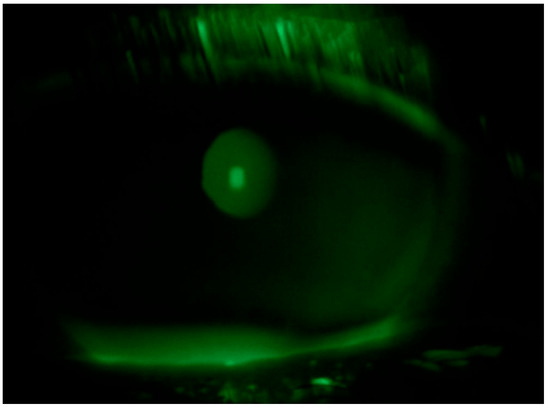

2. Case Description